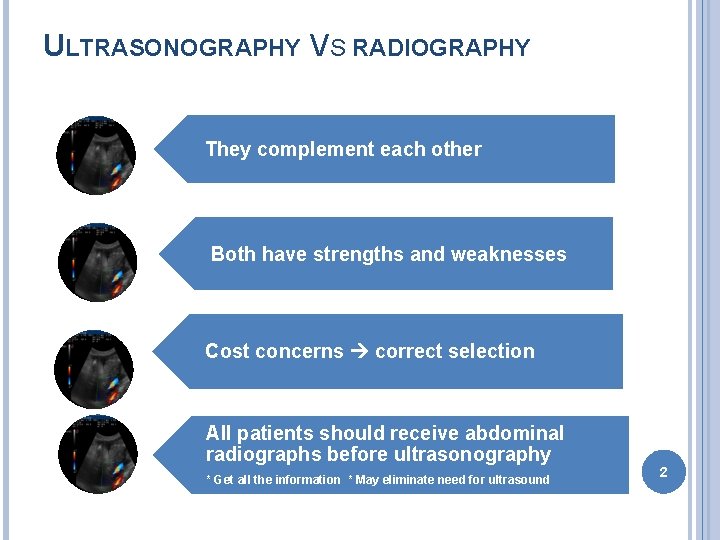

ULTRASONOGRAPHY VS RADIOGRAPHY They complement each other Both have strengths and weaknesses Cost concerns correct selection All patients should receive abdominal radiographs before ultrasonography * Get all the information * May eliminate need for ultrasound 2